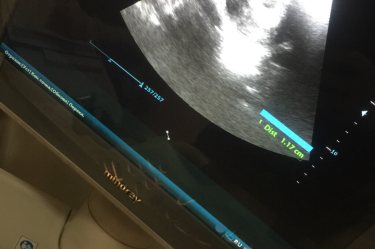

5 недели ❤️